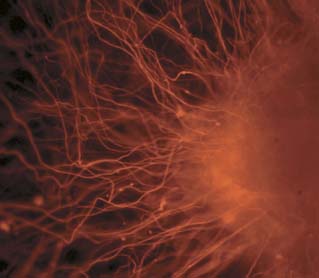

Neurons derived from embryonic stem cells